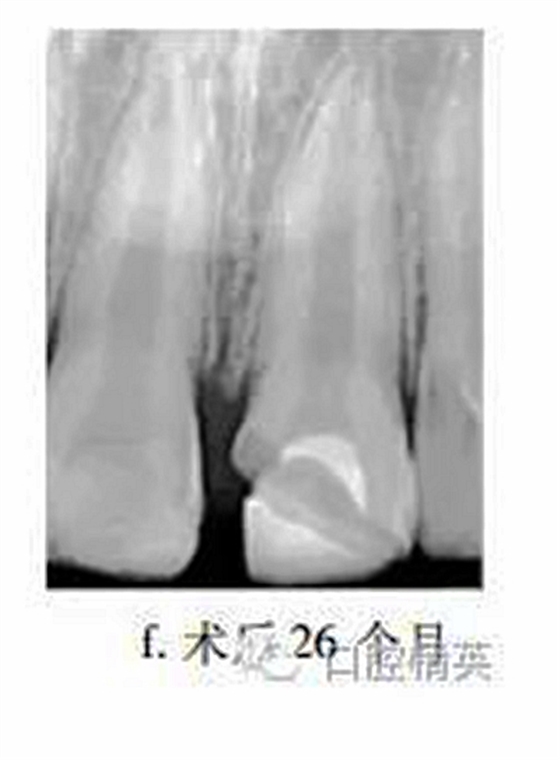

26個月后復查,患牙無不適,牙髓活力測試較正常牙齒略低,冠部充填物部分脫落,X線片示:患牙蓋髓劑下方可見連續(xù)薄層高密度影像,髓腔縮窄,根尖孔聚攏,牙根長度較鄰牙無明顯差異(圖f)?;佳廊コ糠植Aщx子水門汀,備釘?shù)溃魸?,納米樹脂修復冠缺損,調(diào)牙合拋光。

眾多臨床研究表明,MTA用于活髓切斷術(shù)的臨床療效優(yōu)于傳統(tǒng)的蓋髓劑氫氧化鈣,除去MTA較氫氧化鈣具有更好的封閉性以外,低細胞毒性是其另一重要特點。MTA體外實驗中可促進正常牙髓細胞的牙向分化能力,亦能提高成骨細胞的體外骨向分化能力。有學者發(fā)現(xiàn)早期炎癥狀態(tài)下,牙髓干細胞的體外增殖與成牙能力降低,而成骨能力上調(diào),本病例26個月復查X線片中發(fā)現(xiàn)MTA下方有薄層連續(xù)高密度影像,牙根伸長,根尖孔聚攏,提示創(chuàng)傷暴露后的牙髓(干)細胞在MTA誘導下,具有較強的修復能力。